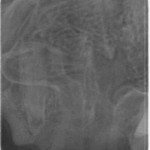

Tænder med TR skal trækkes ud. Men alligvel er det nødvendigt at tage tandrøntgen af alle tænderne for at se om der er andre tænder, der er angrebet af TR.

På Dyretandspecialist kan du læse mere om sygdommen Tooth Resorption (TR/FORL) hos katte. Her kan du både se røntgenbilleder og billeder af tandsygdommens stadier, samt se symptomerne på sygdommen, så du ved, hvad du skal være opmærksom på hos din kat.

Nedenfor kan du se de 8 røntgenbilleder af Shana-Mio´s tænder, som specialtanddyrlægen tog af hendes tænder i 2008, da hun fik konstateret TR/FORL: